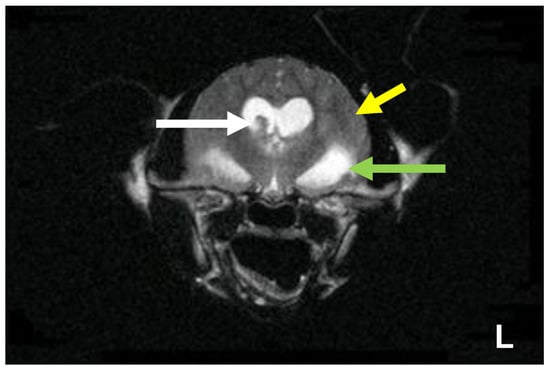

7.4. Diagnostic Imaging in FIP

7.4.2. Advanced Imaging of the CNS: MRI and CT

| Summary of Section 7: Diagnosis of FIP; Section 7.4: Diagnostic imaging in FIP: No specific ultrasonographic or radiographic findings exist for FIP. Ultrasonography (in particular) and radiography can show the presence of effusions. Pneumonia due to FIP that is occasionally reported can be associated with radiographic changes. Ultrasonography can reveal abdominal lymphadenomegaly or lymphadenopathy and/or abnormalities of the liver, spleen, intestines and/or kidneys (which can include a medullary rim sign), depending on which organs are affected. Imaging can also be of use to the direct sampling of abnormal tissues, e.g., fine-needle aspirate for cytology examination to reveal non-septic pyogranulomatous inflammation, or ultrasound-guided needle core (e.g., tru-cut) biopsies can be collected and submitted for histopathology. When a cat is showing neurological signs, the imaging of the brain by magnetic resonance imaging, if available, with contrast, can be useful to demonstrate neurological abnormalities (such as obstructive hydrocephalus, syringomyelia, foramen magnum herniation and marked contrast enhancement of the meninges, third ventricle, mesencephalic aqueduct, and brainstem). A description of computerised tomography findings in cats with neurological FIP has not been published, but MRI is likely to be more sensitive in the detection of subtle intraparenchymal lesions. Advanced imaging of the central nervous system is indicated before performing cerebrospinal fluid sampling to assess the potential risk of herniation. |